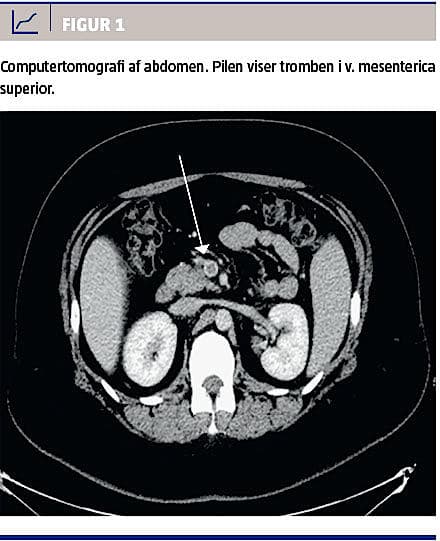

Ved den objektive undersøgelse fandt man kvinden upåvirket, overvægtig med et body mass index på 39 kg/m2 og med diffus abdominal ømhed uden peritoneal reaktion. Biokemisk fandt man forhøjet levertal i følgende koncentrationer med referenceintervaller angivet i parentes: basisk fosfatase på 159 E/l (35-105 E/l), laktatdehydrogenase på 469 E/l (105-205 E/l) og alaninaminotransferase på 95 E/l (10-45), samt forhøjet D-dimer på 3,6 mg/l (< 0,5 mg/l) og S-hCG på 555 IE/l (< 3). En abdominal ultralydskanning, som blev foretaget på mistanke om kolecystolitiasis viste splenomegali. En efterfølgende computertomografi af abdomen viste en trombe intrahepatisk og i v. mesenterica superior (Figur 1). Man påbegyndte behandling med tinzaparin 10.000 IE × 2 daglig og warfarin; p-pillerne blev seponeret. Pga. det forhøjede S-hCG-niveau blev kvinden henvist til gynækologisk afdeling, hvor man ved ultralydskanning fandt en intrauterin levende graviditet svarende til uge 6. Patienten ønskede abort, og der blev foretaget kirurgisk abort i lokalbedøvelse otte dage efter initiering af den antikoagulerende behandling. International normaliseringsratio (INR) på operationsdagen var 1,9. Indgrebet forløb uden komplikationer. Kvinden blev udskrevet til warfarinbehandling i seks måneder og nærmere trombofiliudredning og genetisk udredning.